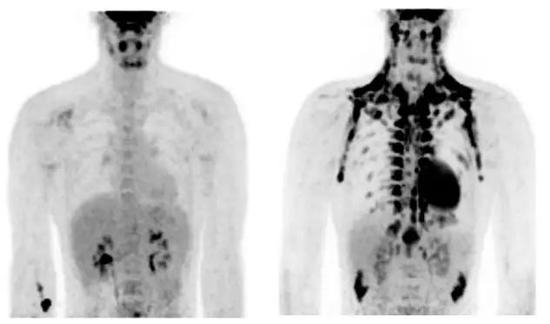

在刚才提到的3篇奠基性论文里,其中一个研究让一些志愿者呆在17-19摄氏度的房间里2小时,然后躺到PET机器里扫描;另一些志愿者则呆在温暖的环境里。结果发现,只需要2小时的低温,志愿者肩颈部脂肪组织的葡萄糖代谢量就增加了15倍。

温度不低时棕色脂肪代谢(肩颈黑色区域)不大(左),受寒后体内棕色脂肪的代谢显著增加(右)